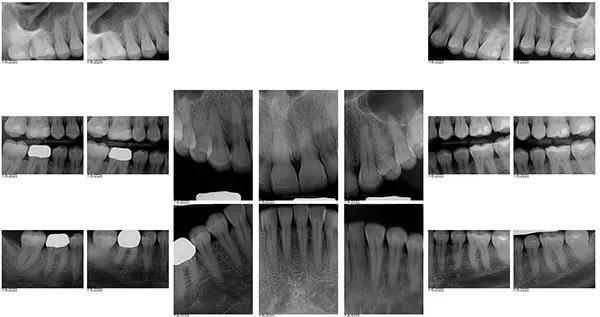

35-летняя пациентка женского пола, наблюдаясь у своего стоматолога с детства выразила заинтересованность в улучшении внешнего вида своих передних зубов, которые в свою очередь, имеют значительные дефекты твёрдых тканей и сколы. Вид улыбки пациентки до лечения "во все зубы" (фото 1); При большом приближении видны сколы во фронтальном отделе зубных рядов (фото 2) Горизонтальный тип стираемости зубов на верхней челюсти (фото 3.). Ее история болезни была отмечена Американским обществом анестезиологов (ASA) II, ввиду ее непереносимости к анестетикам, тем не менее она успешно лечилась с применим препарата Диован. В остальном ее соматическое здоровье никак не отражалось на стоматологическом лечении. В стоматологическом анамнезе у пациенты были выполнены ресторации отдельных зубов и удаление зубов мудрости в подростковом возрасте Представлены прицельные снимки зубов перед восстановительным лечением (фото 4). Также она проходила стоматологическое лечение ранее в детстве. Ее больше всего беспокоил неприглядный вид фронтальных зубов со сколотыми неровными краями на всем протяжении от моляров до первых резцов.

Фото 4